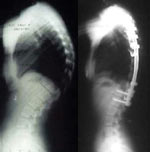

Surgical treatment is effective in reducing the curve; however, it requires fusion of most of the thoracolumbar spine and is only considered as a last resort to avoid or reduce a severe kyphotic deformity (greater than 80 degrees). (Figure 2)

Fig. 2: A last resort - surgical fixation for SD